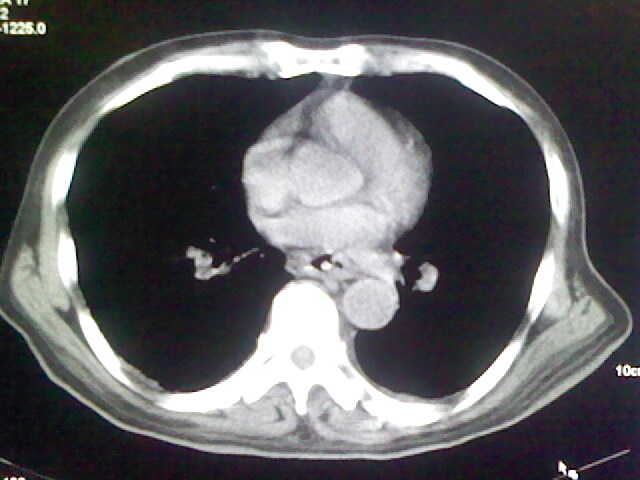

男,70岁,脑出血,长期卧床,左侧背部可触及肿块

继发感染

肺部感染。

支持;肺部感染。

右侧肺部见片状密度增高影,边缘模糊。考虑炎症。另食管壁增厚。

食道里是什么

你放上去的